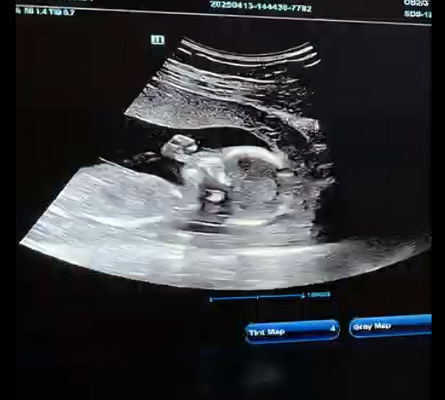

During a scan, a trained sonographer uses a handheld probe that is gently moved across the abdomen. This sends sound waves into the body, which are then converted into clear images displayed on a screen.

The sonographer will then gently move the probe across your stomach. The ultrasound scan Barnsley system displays real-time images, allowing you to see movement, positioning, and heartbeat depending on the stage of pregnancy.

In most cases, you will be able to see your baby’s movement and heartbeat. Image clarity can vary depending on the stage of pregnancy and positioning.